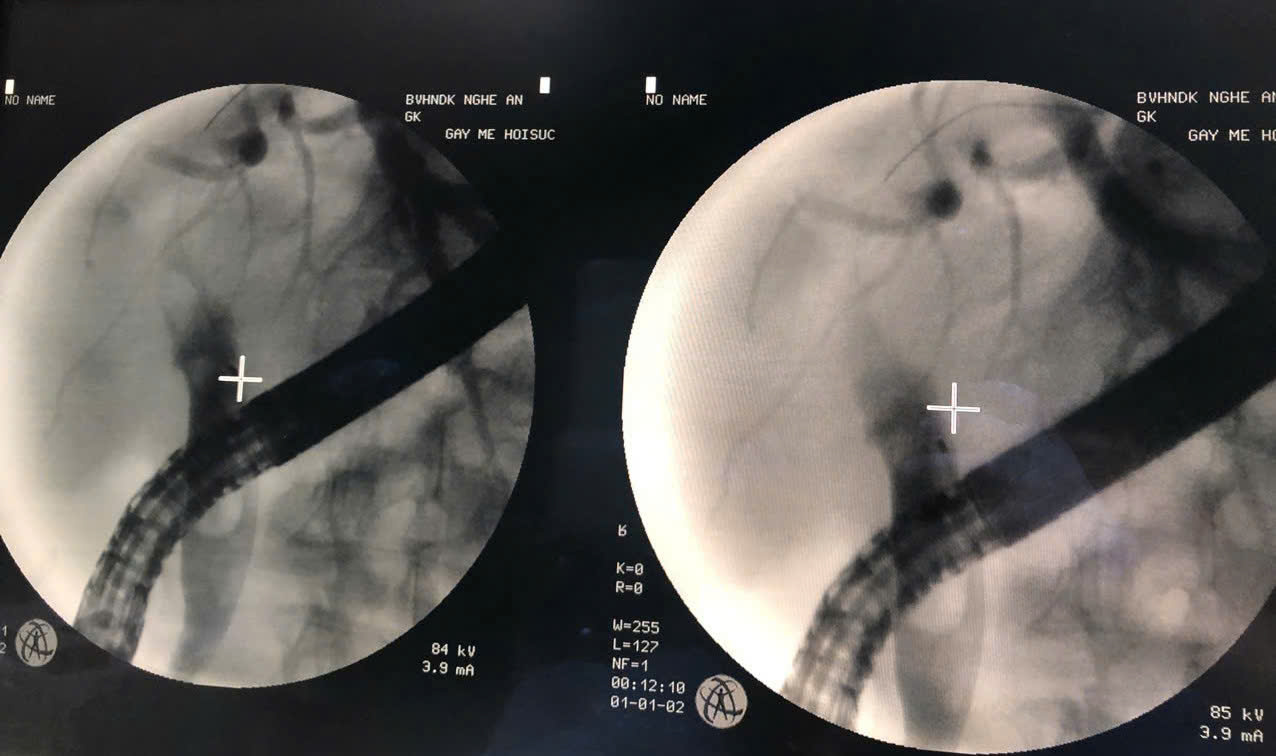

Bệnh nhân nam, 63 tuổi, tiền sử mổ sỏi đường mật, mổ cắt túi mật, đợt này bệnh nhân xuất hiện đau bụng, sốt nhập viện trong tình trạng nhiễm trùng toàn thân. Sau khi thăm khám lâm sàng kết hợp với các phương pháp chẩn đoán hình ảnh, bệnh nhân được chẩn đoán: Nhiễm […]